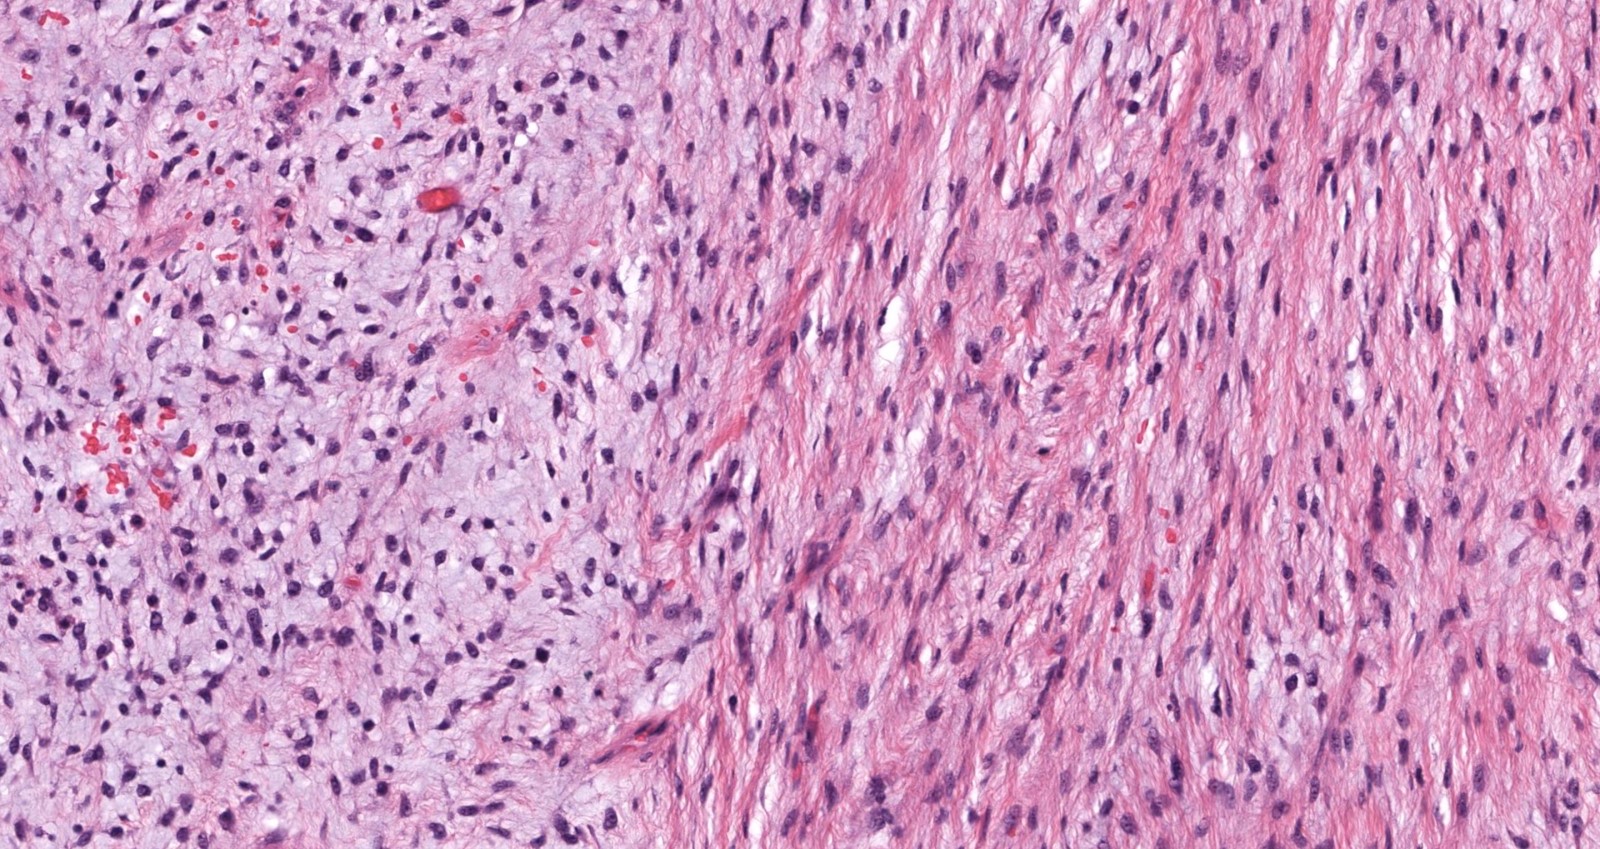

Microscopic (histologic) description

- Low to moderately cellular, bland fusiform or spindled cells with focal to diffuse whirling in heavily collagenized stroma with abrupt transition to myxoid areas

- 45% have epithelioid areas

- Occasionally has areas of increased cellularity, atypia, necrosis or mitotic activity characteristic of intermediate to high grade sarcoma

- Recurrences may show increased cellularity and mitotic activity